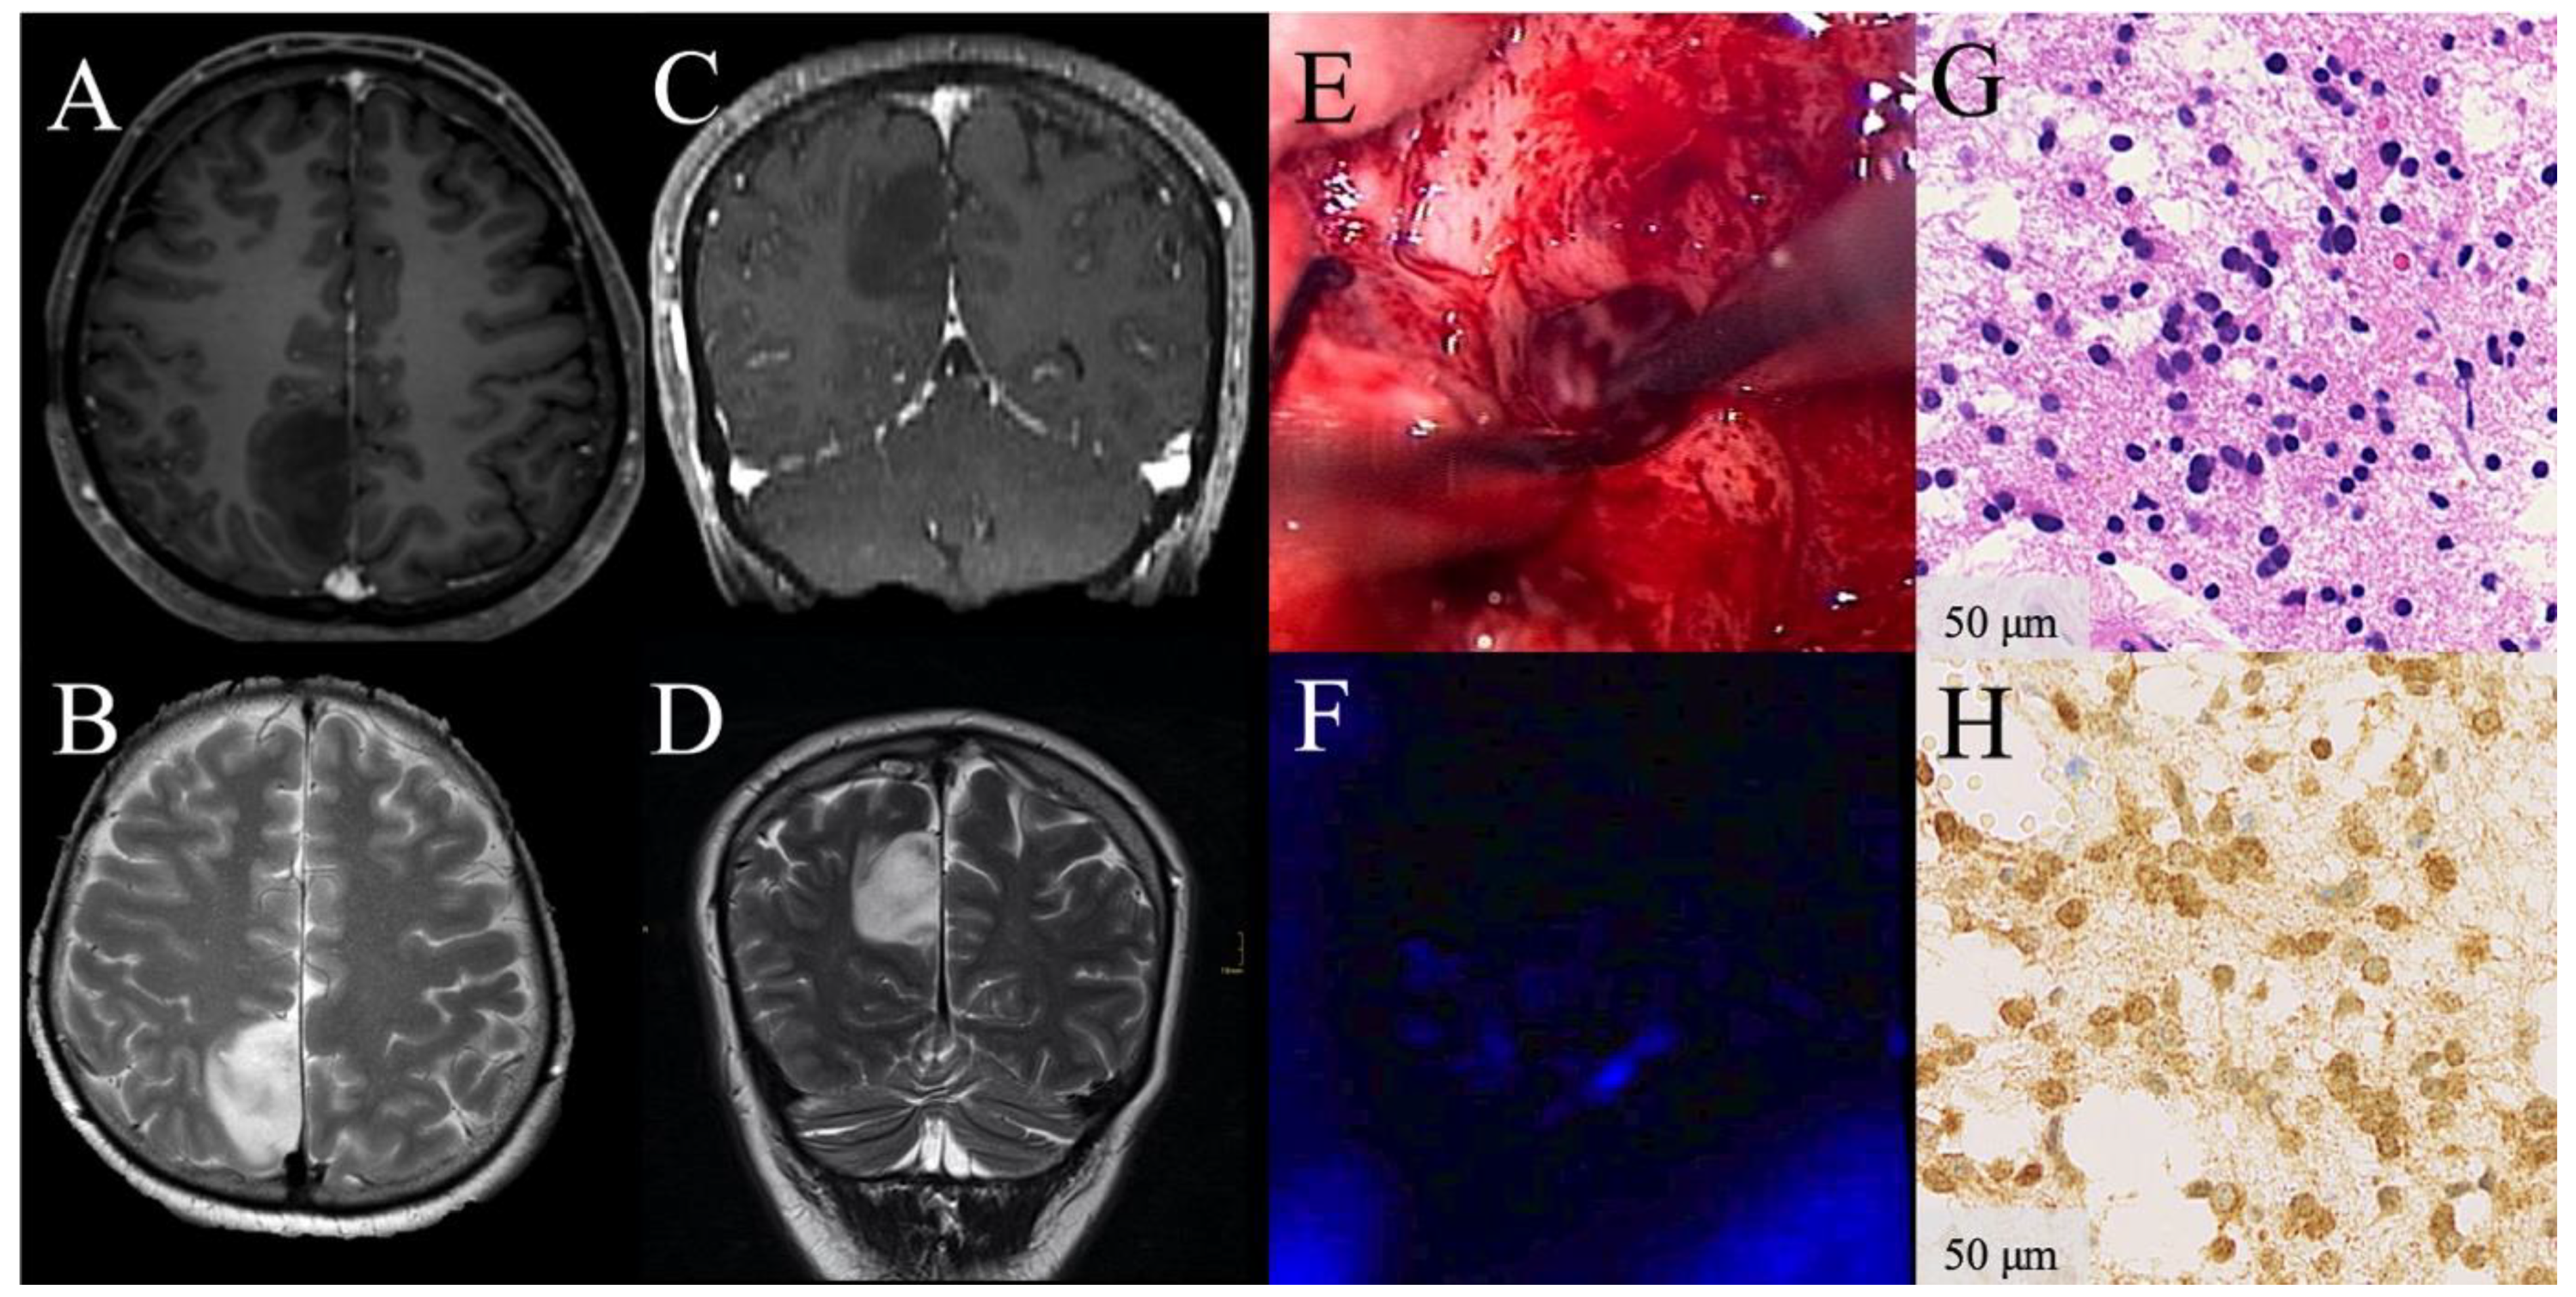

3.2. Tumor Resection and Intraoperative 5-ALA Fluorescence